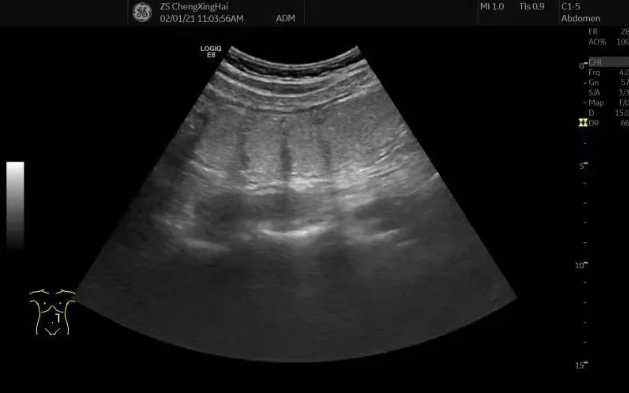

超声显示充盈的结肠及动态充盈的过程